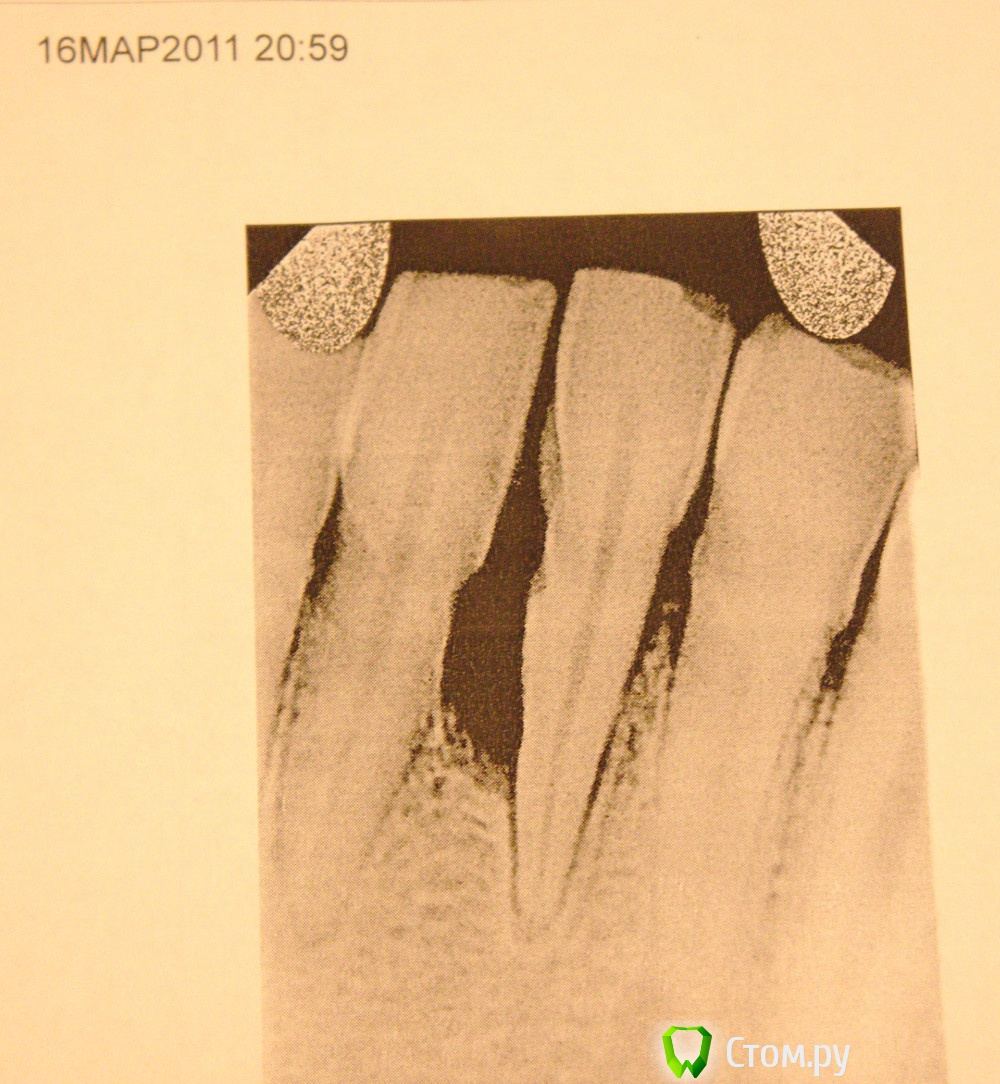

humbert Опубликовано 18 августа, 2014 Поделиться Опубликовано 18 августа, 2014 Я так понимаю у меня пародонтит или пародонтоз (путаю я их). Десна кровоточат, запах изо-рта. Передний нижний зуб давно шатается, десна опущена. Раз-два в год десна воспаляется. Но всегда проходит через пару-тройку дней. В этот раз зуб шатается очень сильно - достаточно дунуть. Десна опухла и есть невозможно, жевать что-то точно нельзя. Случилось это из-за очень жесткого персика - погрыз и утром десна взбунтовалась. Очень быстро образуются камни, хотя стараюсь чистить два-три раза в день зубы. Есть даже Waterpik WP-100 - чищу им полость рта. Делал снимки в 2011 году, сказали, что кость съедена или из-за травмы в детстве отколот кусок (часто в морду лица получал).Сегодня сделал еще один снимок. Врач предложила два варианта: 1. спасение зуба - пульпирование, чистка от камней, шинирование.2. удалить зуб (зуб вроде как здоровый), чистить все и шинировать крайние зубы от удаленного. Зуб жалко, но кушать хочется и боль достала. Я понимаю, что по снимкам и рассказам мало что можно сказать, но вот пока вечер, хочу получить консультацию других врачей. Ссылка на комментарий